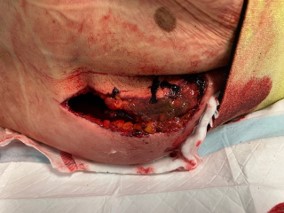

Morel - Lavallee Lesion

Definition

Skin degloving

- predisposes to infection

- found on the thigh in lateral compression fractures

- found in the lumbar area in APC or vertical shear

Morel Lavalle

Morel-Lavallee

Beckmann et al Emerg Radiol 2016

- ML lesions seen in 12% of pelvic fractures based on CT

- most common in vertical shear (34%)

- occur in 12% of APC and LC fractures

Compound wounds

Compound pelvis 2Compound Pelvis 1